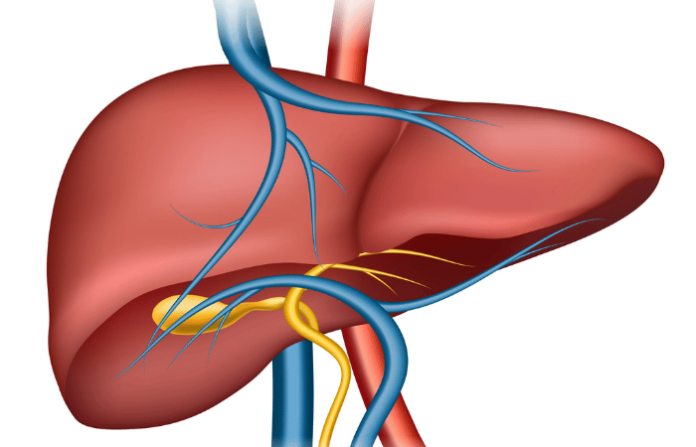

चयापचयामधील बिघाडामुळे फॅटी लिव्हरचा आजार होण्याचे प्रमाण हे दिवसागणिक वाढू लागलेले आहे. त्यामुळेच ही एक मोठी जागतिक आरोग्य समस्या म्हणून आता समोर येत आहे. लॅन्सेटने केलेल्या नवीन संशोधनानुसार, गेल्या तीन दशकांमध्ये या रुग्णांमध्ये लक्षणीयरीत्या वाढ झाल्याचे निदर्शनास आलेले आहे.

‘द लॅन्सेट गॅस्ट्रोएन्टेरोलॉजी अँड हेपॅटोलॉजी’मध्ये प्रकाशित झालेल्या एका अभ्यासानुसार, २०२३ मध्ये जगभरातील सुमारे १.३ अब्ज लोक यकृताच्या आजाराने ग्रस्त होते. १९९० च्या तुलनेत ही तब्बल १४३ टक्के वाढ असून, यावरून आपल्याला जागतिक पटलावर या आजाराचे प्रमाण किती वाढलेले आहे याचा अंदाज येतो.

पीटीआयने दिलेल्या वृत्तानुसार, संशोधकांनी इशारा दिला आहे की, २०५० पर्यंत यकृता संदर्भातील आजारांचे प्रमाण आणखी वाढणार आहे. हे प्रमाण हे तब्बल १.८ अब्ज लोक या आजाराने ग्रस्त होतील असा अंदाज व्यक्त करण्यात आलेला आहे. या आजाराच्या वाढीचे मुख्य कारण म्हणजे वेगाने वाढणारी लोकसंख्या, लठ्ठपणाचे वाढते प्रमाण आणि उच्च रक्तशर्करा व चयापचय विकारांच्या घटनांमध्ये होणारी वाढ. शहरीकरण, बैठी जीवनशैली आणि अयोग्य आहार पद्धतींशी निगडित जीवनशैलीतील बदल हेच या आजाराचे मुख्य कारण जगभरामध्ये असल्याचे, निदर्शनास आलेले आहे. अभ्यासात असे आढळून आले आहे की, जगाच्या इतर भागांच्या तुलनेत उत्तर आफ्रिका आणि मध्य पूर्वेसारख्या प्रदेशांमध्ये, यकृताचा आजार असण्याचे प्रमाण हे सर्वाधिक आहे.